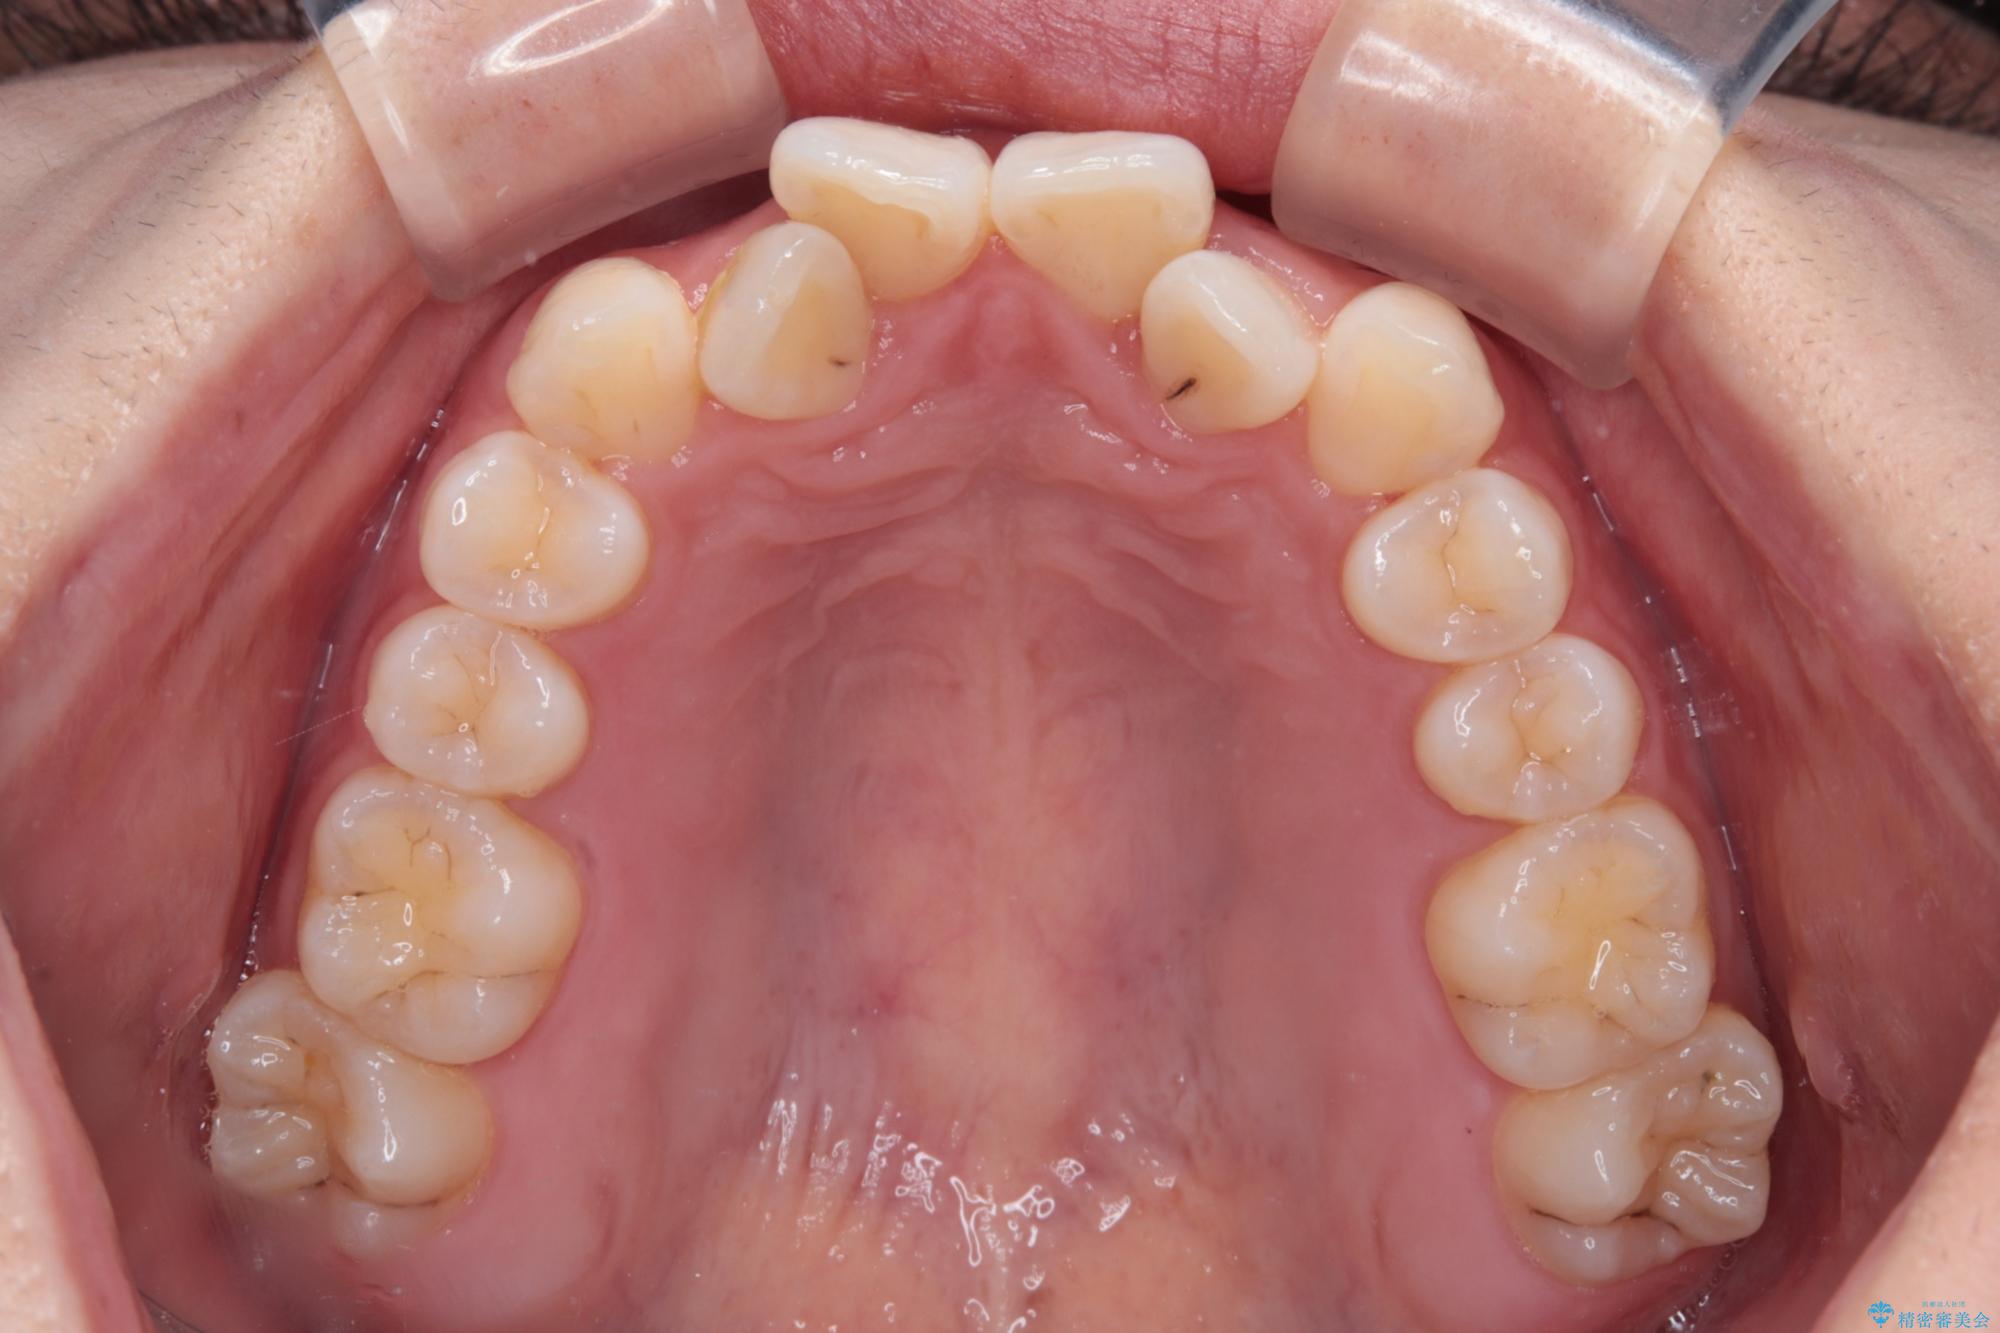

- 上顎前歯のクロスバイトを気にして来院された患者様です。

ワイヤー矯正でもマウスピース矯正でも対応可能でしたが、マウスピースによる自己管理に一切の自信がないとのことで、ワイヤー装置にて矯正治療を行うこととしました。

装置の外見を気にしていましたが、短期間で治療を終えることができるだろうと伝えると、安価であるメタルブラケットを選択されました。

想定通り、1年強で綺麗に仕上げることができました。